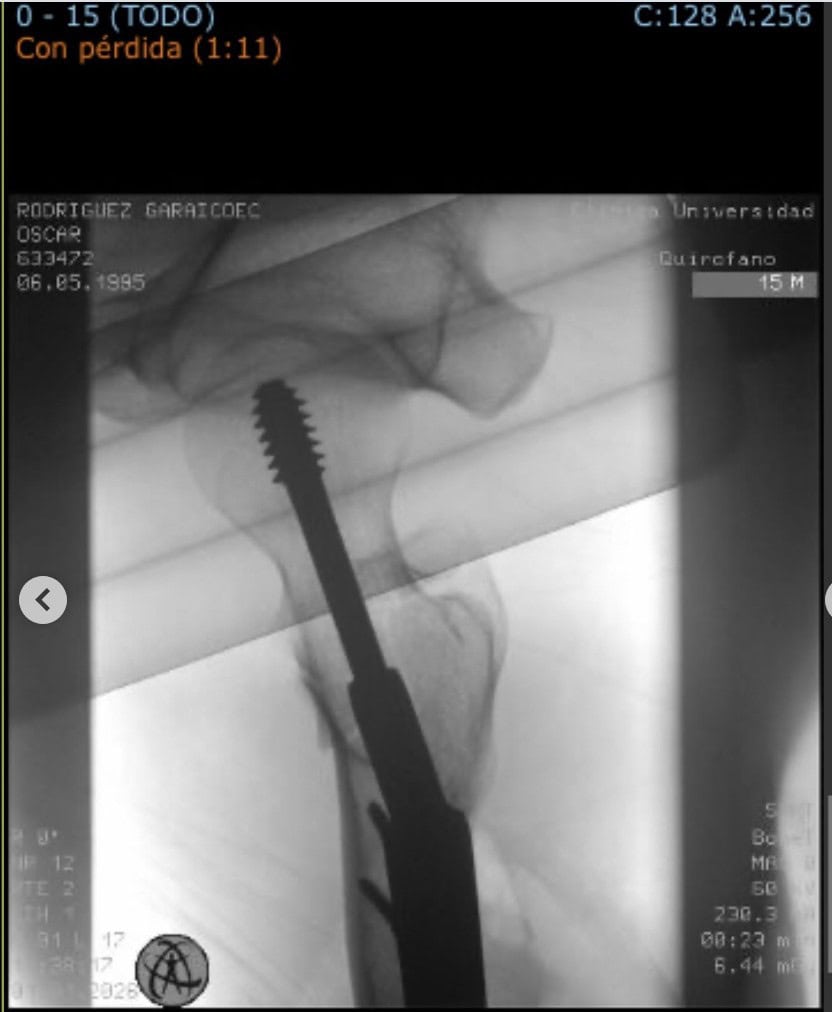

El propio ciclista utilizó sus redes sociales para dar detalles sobre el suceso, manteniendo una actitud sorprendentemente positiva pese a la gravedad de la situación. Rodríguez explicó que el accidente se produjo por una caída que en otras circunstancias podría haber sido anecdótica, pero que resultó en una fractura de la parte superior del fémur derecho. Agradeció a los doctores Ignacio Lorenzo, Díaz de Rada y Valentí Azcárate por su rápida atención en un día tan señalado. Su mensaje fue claro y combativo: "Volveré rápido y bien".

En el caso de deportistas jóvenes y activos (en términos médicos, un hombre de 30 años lo es), el tratamiento estándar suele ser la osteosíntesis, que consiste en fijar los fragmentos del hueso mediante tornillos o placas, en lugar de un reemplazo total de cadera (prótesis), que es más común en personas mayores. El objetivo es preservar la anatomía original del fémur para permitir un retorno al deporte de alto impacto. Sin embargo, la consolidación ósea es un proceso biológico que no se puede acelerar artificialmente y suele requerir, como mínimo, de seis a ocho semanas antes de aplicar cargas significativas.

Generalmente, en deportistas jóvenes (menores de 50-60 años), se opta por una osteosíntesis. Esto implica reducir la fractura y fijarla con tornillos canulados o placas, preservando la cabeza femoral del paciente, a diferencia de una prótesis total de cadera que reemplaza la articulación.